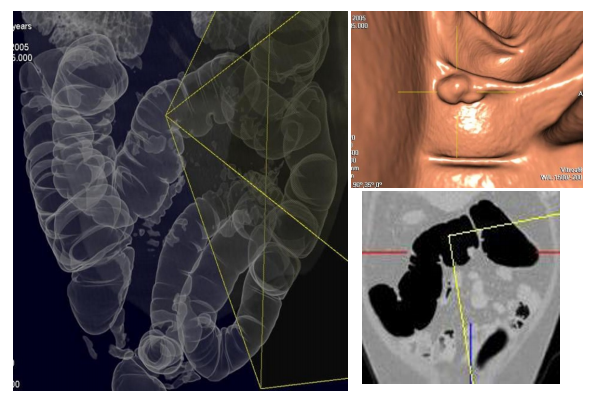

The example of CT colonography. There is a small polyp.

I think you probably do not have much. This image technique is getting a CT and reconstructing the image to find a lesion in the large intestine, like colonoscopy.

There are 2D and 3D methods for reconstructing and reading images. Both are used to read the images.

Even if the endoscope is not inserted directly into the colon, the radiologist can evaluate the colon by moving the images like performing real colon endoscopy. Therefore, it is called 'virtual colonoscopy'. Patients just have to take a short CT scan after preparation (rectal tube insertion and inflation of the colon).